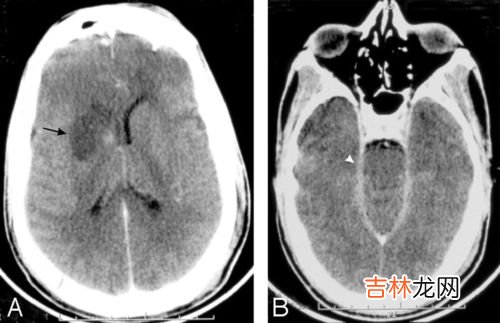

当噬脑变形虫进入人体后 , 它们会吃掉包围在嗅球周围的组织,使患者失去嗅觉以及味觉,同时会引起人体高烧,头痛,呕吐等症状 。

随后 , 噬脑变形虫会沿着嗅觉神经迁徙到人体的大脑皮质、小脑以及其他部位,导致大脑出现损害 。而大脑是控制人体行动能力,记忆能力,视觉等一系列高级复杂活动,由于噬脑变形虫的啃食,会导致患者出现精神错乱、幻觉以及肢体痉挛等一系列临床症状,最终会引发人体死亡 。